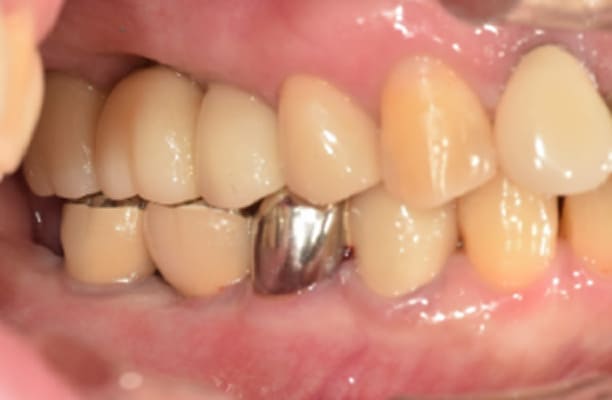

临床案例

-

术前 -

术后